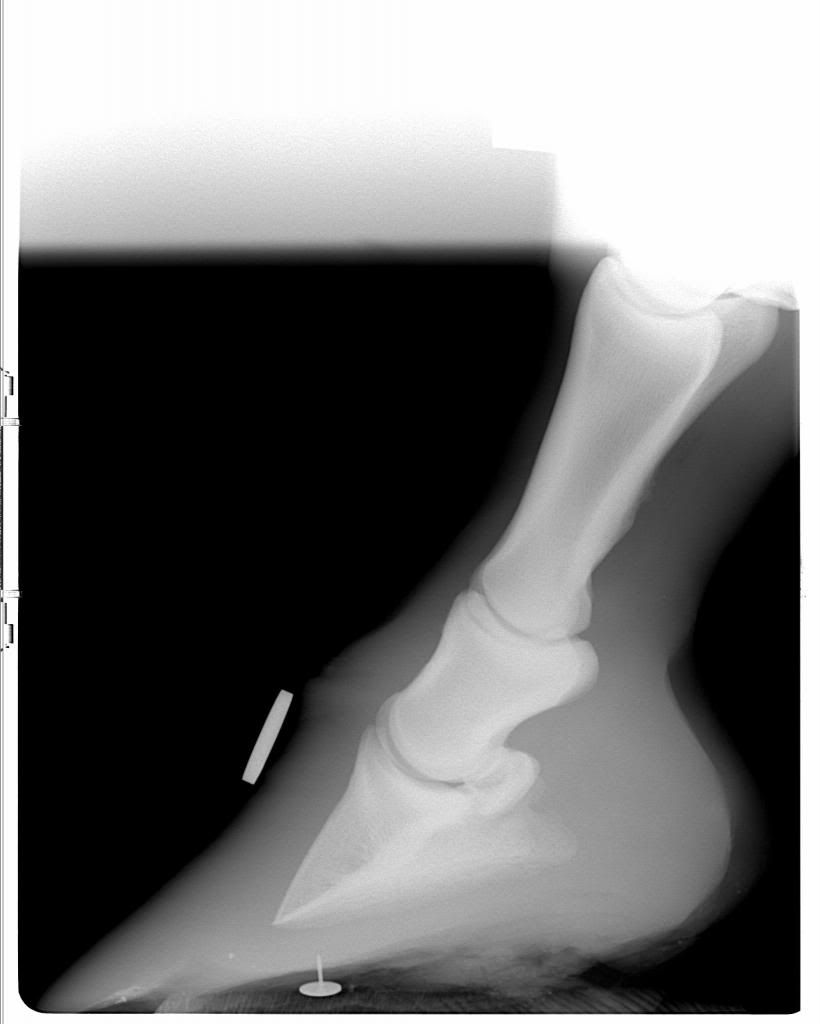

Just out of interest, I have a set of X rays taken of my horse's feet from around 2 years ago, after she had had laminitis.

Even though she was barefoot, I didn't really pay much attention to the feet side of things and left it to my farrier/vet at the time, therefore I don't feel as though I learned anything from the experience and would really value you barefooters comments on what you can see. Now I am very interested in this subject!

As I mentioned, these are not current, they are two years old and my horse was trimmed accordingly, but I would love to hear your thoughts and opinions and anything you can gleam from them, if only as a learning exercise.

Left Fore

The fore hooves are very, very long in the toe. She would have had very stretched white lines. Even on the x-rays you can see the angle that the hoof should have been (under the coronet). If you take that angle down, you can see that the hooves would be much smaller, however the pedal bone would still be rotated down.

All FOUR feet are very long in the toe and flat.

I would say that, even without the pedal bone rotation the horse was metabolically compromised and careful attention needed paying to both diet and trimming.

It was certainly an eye opener and from that day onward I became obsessed with her diet, had the farrier out at least every 6 weeks and he trimmed them to help realign the rotation - I was told it was 9 degrees at the time by the vets.